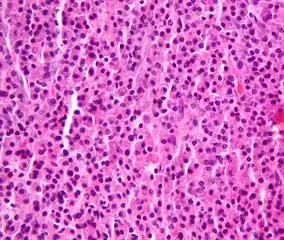

Plasmacytoma/pathology Micrograph of a plasmacytoma.

Micrograph of a plasmacytoma. Micrograph of a plasmacytoma. H&E stain.

Micrograph of a plasmacytoma. H&E stain.